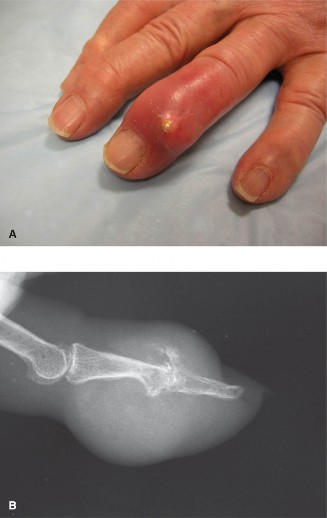

CASE 12 A 24-year-old, law student injured her left index finger during a volle…